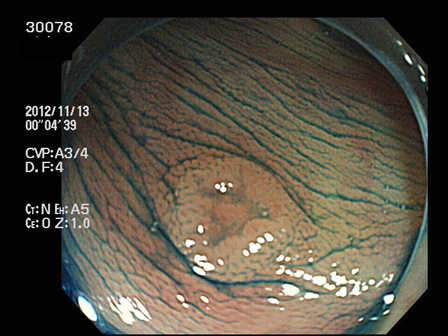

上記100名より抽出した平坦・陥凹型腺腫(=癌化の危険が高いが見落としやすい病変)の内視鏡写真

30001 30005 30008 30014 30016 30019 30020 30022 30023 30024 30025 30026 30027 30028 30029 30031 30033 30034 30036 30038 30044 30045 30047 30049 30051 30053 30055 30056 30057 30058 30059 30060 30066 30069 30072 30073 30074 30076 30077 30078 30079 30080 30081 30082 30083 30084 30085 30087 30088 30092 30097 30098・・・・・・・の52名